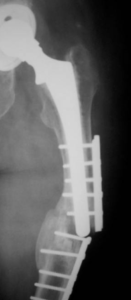

- Περιπροθετικό κάταγμα στην περιοχή του ισχίου στο επίπεδο του εμφυτεύματος.

- εσωτερική οστεοσύνθεση με πλάκα και αρκετή ελαστικότητα στο σύστημα.

- Ο ασθενής είναι σε πλήρη δραστηριότητα σε διάστημα δυόμισι μηνών μετά το κάταγμα.